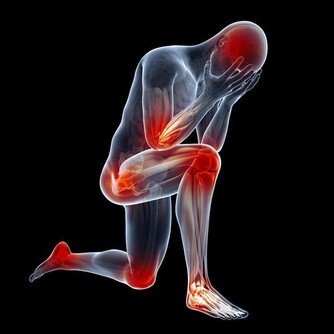

必知!身體90%的疼痛都和「脖子僵硬」有關,沒想到睡覺不用枕頭才是最健康的! 不管什麼職業都可能受脖頸酸痛之苦,正值工作高峰期的上班族、社會新鮮人,甚至正在讀書的學生。常見的問題都是頭痛、肩膀酸痛、背部疼痛、手部麻痹或是心理層面的情緒困擾,問題多而複雜。但是你知道這一切其實都是和脖子有關嗎? 「頭痛、專注力低落」乍看之下看脖子無關,任何人都不太會把兩者連想在一起,可是這些症狀其實都是因為脖子出現異常。脖子一旦出了問題,症狀會多到超乎想像。脖子是遍布全身的神經彙整後,在往上串連腦部的部位。裡面除了有食道、氣管和血管之外,還有主掌全身的神經束,也就是「脊髓」。運送血液到大腦的頸動脈、運食物到胃部的食道、維持呼吸的氣管,以及全身神經活動的脊髓,這些都是維持生命的重要器官。

只要改善脖子僵硬的問題,像是後腦勺產生鈍痛、重聽、腰痛、五十肩或耳鳴暈眩,幾乎90%的疼痛問題都會消失。 而如何能夠改善脖子僵硬呢?其實許多人推崇的「趴睡」是最傷脖子的,最健康的是睡覺不用枕頭。睡覺的姿勢錯誤會造成脖子的負擔,主要原因出自於枕頭。不可否認的,枕頭是維持脖子建康極為重要的因素,不過嚴格來說,睡覺不用枕頭才是對脖子最好的睡法。